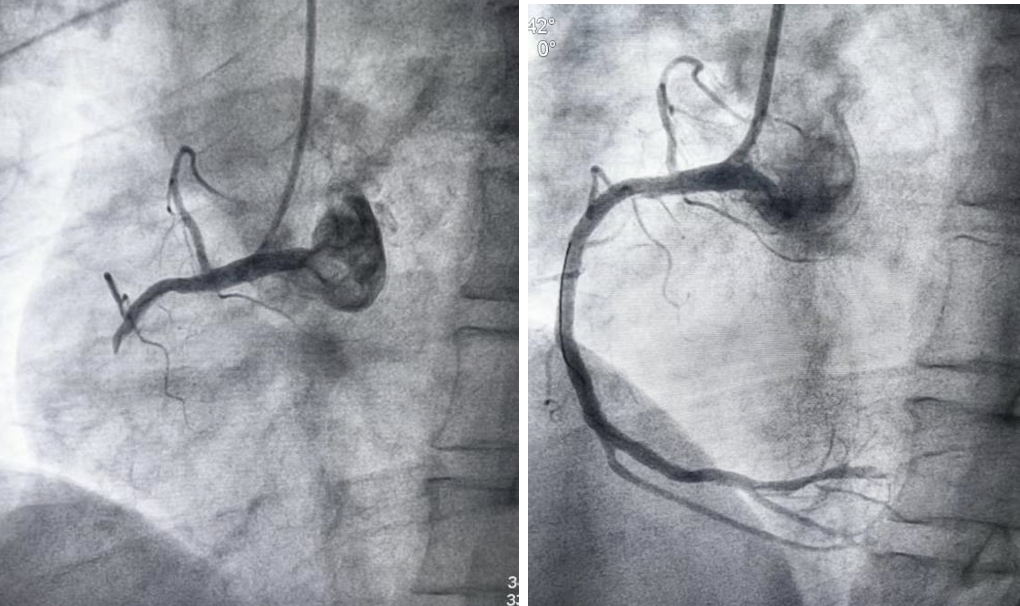

术中心内科路映攀主任及贾凯剑主治医师发现其右冠主干闭塞,遂行经皮冠状动脉腔内抽栓术、血管成形术及药物洗脱冠状动脉支架置入术,术后血流达到3级再通。

右冠主干闭塞(术前) 右冠主干再通(术后)